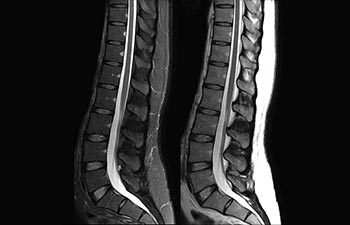

Encuentre la aplicación clínica adecuada a sus necesidades